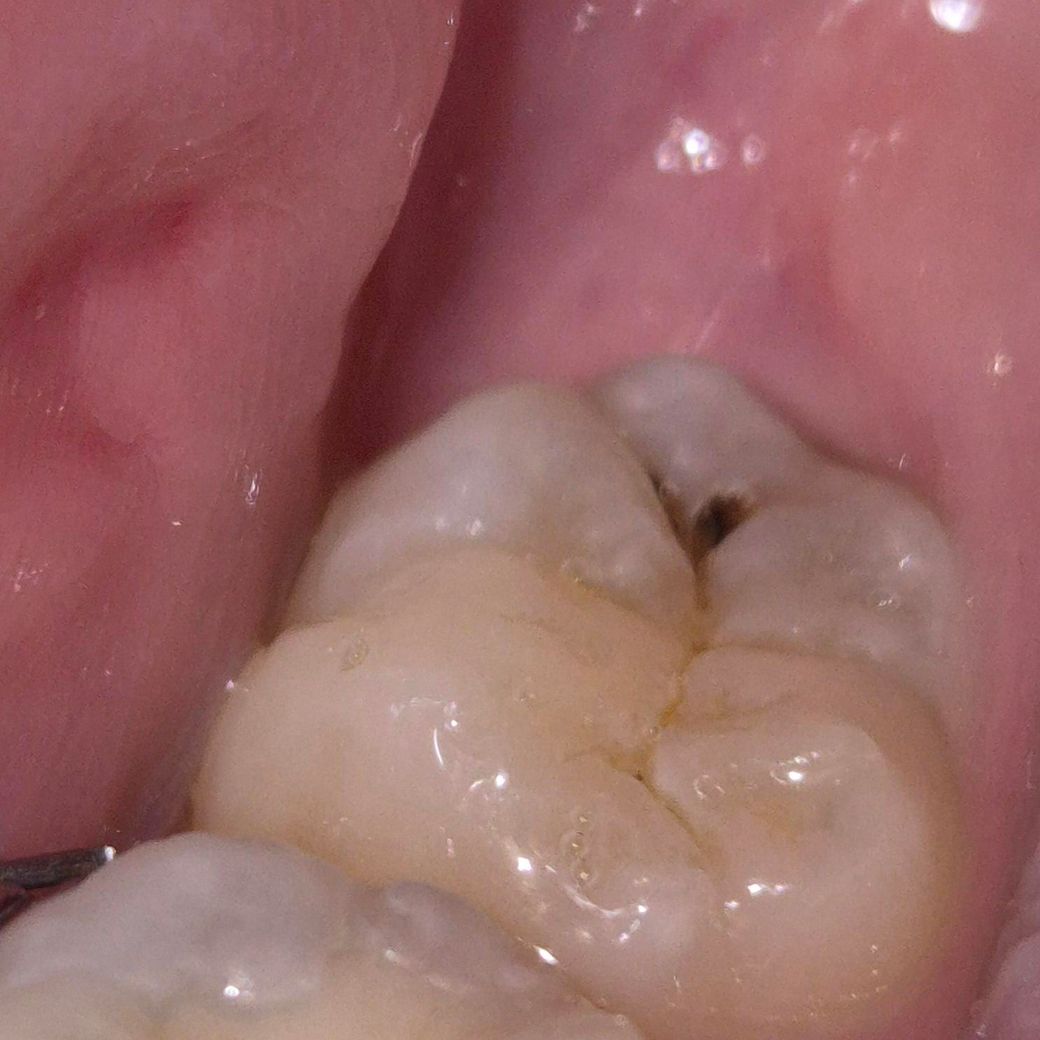

지금 치료 안해도 되는 가벼운 충치인가요?

교정중인데 사랑니에 충치가 생겼어요.

치과에서는 깊은 충치는 아니라 치료 안하고 냅둬도 된다고 하셨는데 진짜 괜찮나요?

(사랑니가 바르게 나서 빼지 않고 일반치아로 사용할 계획이라 발치는 안 하기로 했어요)

• 1번 째 사진

사랑니를 빼는 것이 아니라면 바로 치료를 받으시는 것이 좋아보입니다. 충치가 꽤 큰편입니다.

사진상을 보면 충치가 진행되는 중이고 상당히 깊을것같습니다. 치과에 가셔서 엑스레이를 찍어보시고 상담을 받아보셔야될것같습니다.

초기 충치의 단계는 아닙니다. 충치가 어느정도 진행이 되어 법랑질구조의 파괴는 일어났습니다. 개인적인 판단으로는 사랑니를 발치하지 않고 충치치료하여 쓸 계획이라면 너무 늦지 않게 치료하는 것이 좋을 것 같습니다.

다만 이러한 판단(충지 진행 정도, 치료 필요 여부)은 치과의사마다 다를 수 있고 더군다나 사랑니이기 때문에 보통은 충치가 있으면 치료를 하지 않고 빼는 경우가 많습니다.